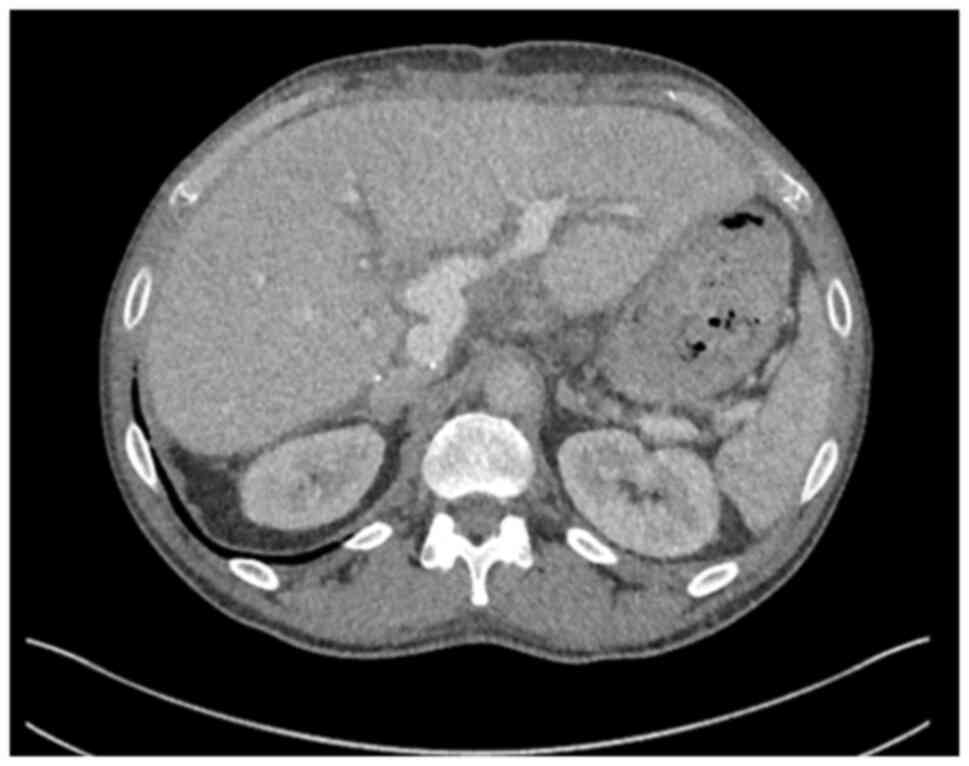

In January, 2025, the patient developed multiple intrahepatic and peritoneal metastases (Fig. 11). Notably, HER2 overexpression was confirmed in the most recent metastatic specimen, prompting initiation of palliative systemic therapy with zanidatamab, a bispecific HER2-targeted antibody. HER2 immunohistochemistry was performed on 4-µm paraffin-embedded sections using the BOND ORACLE HER2 IHC System (cat. no. DS9800 Leica Biosystems), an automated, standardised assay in which all steps were executed according to the manufacturer s validated protocol.

Axial computed tomography imaging

illustrating multiple liver metastases in 2025, occurring 6 years

following liver transplantation and 8 years following the initial

diagnosis of PSC-related hilar cholangiocarcinoma.

Figure 11

Axial computed tomography imaging illustrating multiple liver metastases in 2025, occurring 6 years following liver transplantation and 8 years following the initial diagnosis of PSC-related hilar cholangiocarcinoma.

The primary hilar cholangiocarcinoma specimen resected in 2017 was retrospectively retrieved and subjected to the same HER2 IHC protocol, confirming HER2 overexpression in the original tumour (Fig. 12). Although HER2 testing was not routinely performed in 2017, the concordant HER2-positive status of both primary and metastatic sites supports the rationale for HER2-directed therapy in this patient.